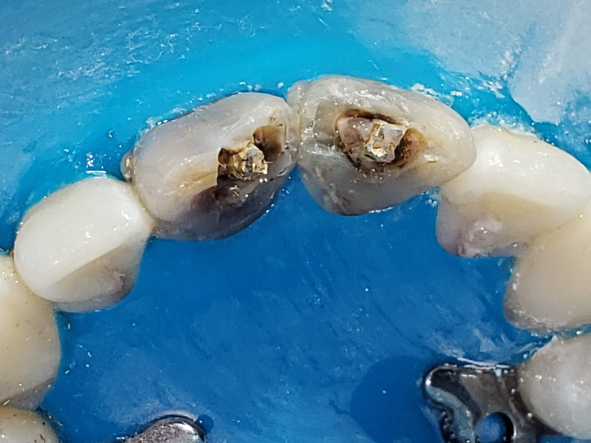

Remoción de los tornillos

Se realiza aislamiento absoluto y remoción del composite que fijaba los tornillos (Fig 4-5). Posteriormente, se procede a la extracción cuidadosa de los mismos con una pinza hemostática tipo Kocher, girándolos en sentido antihorario (Fig.6). Este procedimiento se realizó con suma precaución para evitar la fractura de las raíces dentarias, ya que los tornillos roscados (fig.7) pueden inducir microfisuras o causar estrés interno en la dentina radicular (Silva et al., 2020).

Fig. 4-5 Eliminacion de composite vista de tornillos

Fig. 5